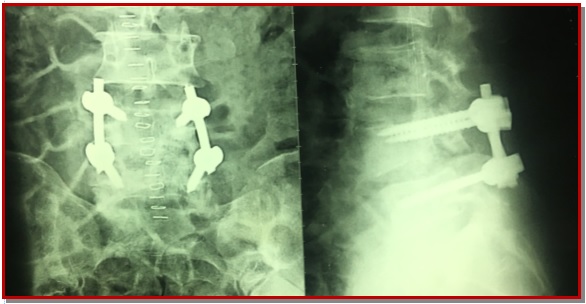

Spondylolisthesis is forward slipping of upper vertebra in relations to its lower one, commonest is L4-L5. The ideal surgical treatment of spondylolisthesis is still controversial. Posterior lumber interbody fusion with pedicle fixation is one of treatment choices for the lumber spondylolisthesis. Forty patients who operated through posterior lumber interbody fusion and pedicle screw fixation by single surgeon was included from January 2012 to March 2015. Periodical follow-up was done both clinically and radiologically up to 6 months. Patient outcome was completed based on pain relief graphic rating scale and Oswestry disability index. In our series, the excellent outcome were 25 patients (62.5%), good were 12 patients (30%), and fair were 3 patients (7.5%). There were no poor outcome and no new neurological deficit. This study concludes that posterior lumber inter-body fusion with pedicle is an effective treatment for the lumber spondylolisthesis. It helps to maintain the biomechanics, associated with less complication and improve the quality of life of patient.